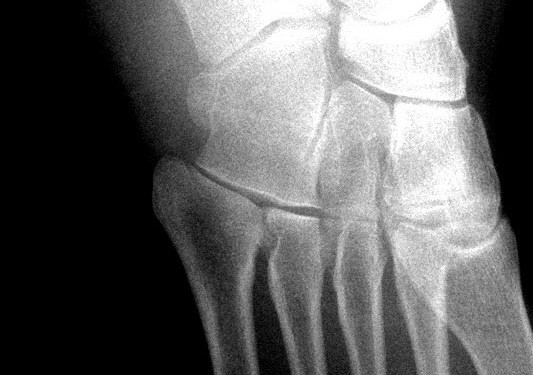

1. Lateral malleol kırıkları; inversiyonla birlikte görülen basit avulsiyon kırıklarından ayrışmayla birlikte deplase kırıklara kadar çeşitlilik gösterir. Düz grafiler tanı koymak için genelde yeterlidir

Düz grafiler tanı için sıklıkla yeterlidir.